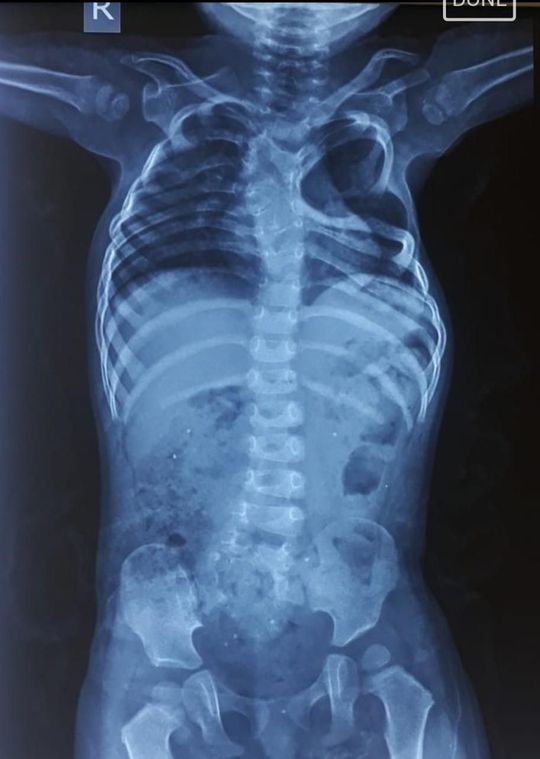

which condition is this?? pls tell me....

Scoliosis

It is related to spine disease.... what about that 2nd and 3rd ribs??